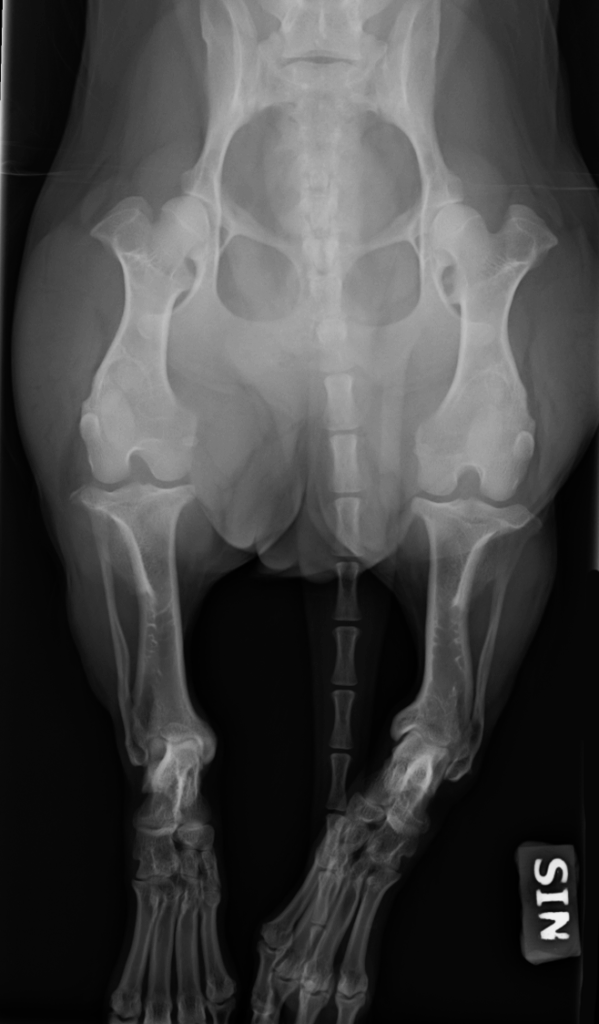

Kuva 1 on selällään otettu röntgenkuva karkeakarvaisen mäyräkoiran takajaloista, jossa muutos näkyy selvästi. Mitä aikaisemmin sisäpuolen kasvulinja sulkeutuu, sitä enemmän jalka vääntyy ja sitä pahempia ovat oireet. Useimmiten pes varus on vain toisessa jalassa, mutta se voi olla myös molemminpuolinen.

Kuva 1: Vasemman (SIN) takajalan pes varus yhdeksän kuukauden ikäisellä karkeakarvaisella mäyräkoiranartulla. Jalan alaosa taipuu kintereestä voimakkaasti sisäänpäin.